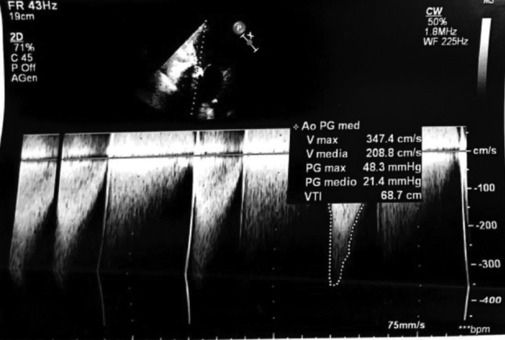

The pandemic changed the type of patients. The concept of "patient at the center" became concrete. The execution of simple consultancy was overcome to create effective collaboration and fruitful exchanges between specialists. The "Heart Team" model is on increasing affirmation. The TEAM-BASED approach in the cardiology field is successfully used in patients suffering from ischemic heart disease and valvulopathies for the choice of possible treatments. Degenerative type Sao is the most frequent valvulopathy among the valvulopathies in Western countries and its incidence is correlated with age. In high-risk patients, percutaneous valve replacement (transcatheter aortic valve implantation) is the most valid therapeutic option. The implantation of biological prostheses raises the problem of both degeneration and dysfunction of the prosthesis itself over time in subjects of advanced age and with comorbidities. In this scenario, valve-in-valve (VinV) is a valid therapeutic alternative in high-risk patients. A clinical case of aortic prosthetic degeneration, as an outcome of endocarditis, treated with VinV is presented. The therapeutic decision was made by an "Electronic Heart Team" which represents a further evolution of the treatment pathways and reduces the distance between the specialists in "Hub" Centers and the "Spoke" center.